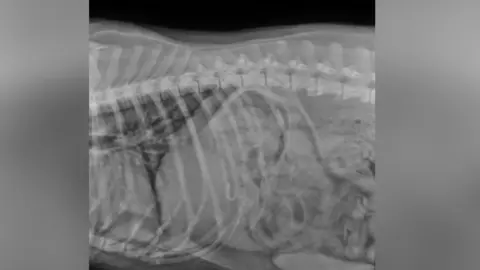

Ricardo Silva, from Aldgate Veterinary Practice in Bridlington, said he had seen two cases this year of fish hooks, one stuck in a dog's lip and one that had been swallowed.

Aldgate Veterinary Practice, BridlingtonMr Silva said treatment for fish hook accidents could be costly for dog owners, adding: "Because we live in a coastal town it's just something that we witness on a fairly regular basis."